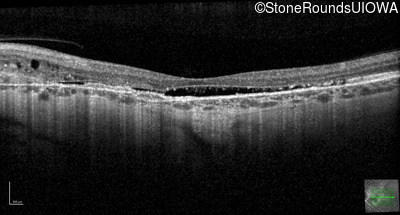

Optical Coherence Tomography - Right - 20/25 +2 sc

Exemplar / OCT Stack

OCT Stack

Optical Coherence Tomography - Left - 20/30 -2 sc